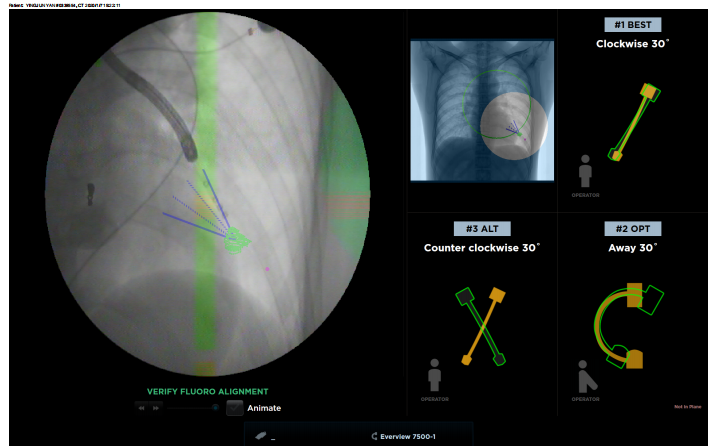

最后,在手把手演示环节,印度专家在Broncus临床应用同事指导下体验操作LungPoint增强现实导航,充分了解导航技术,迅速掌握导航操作技巧。

手把手演示环节